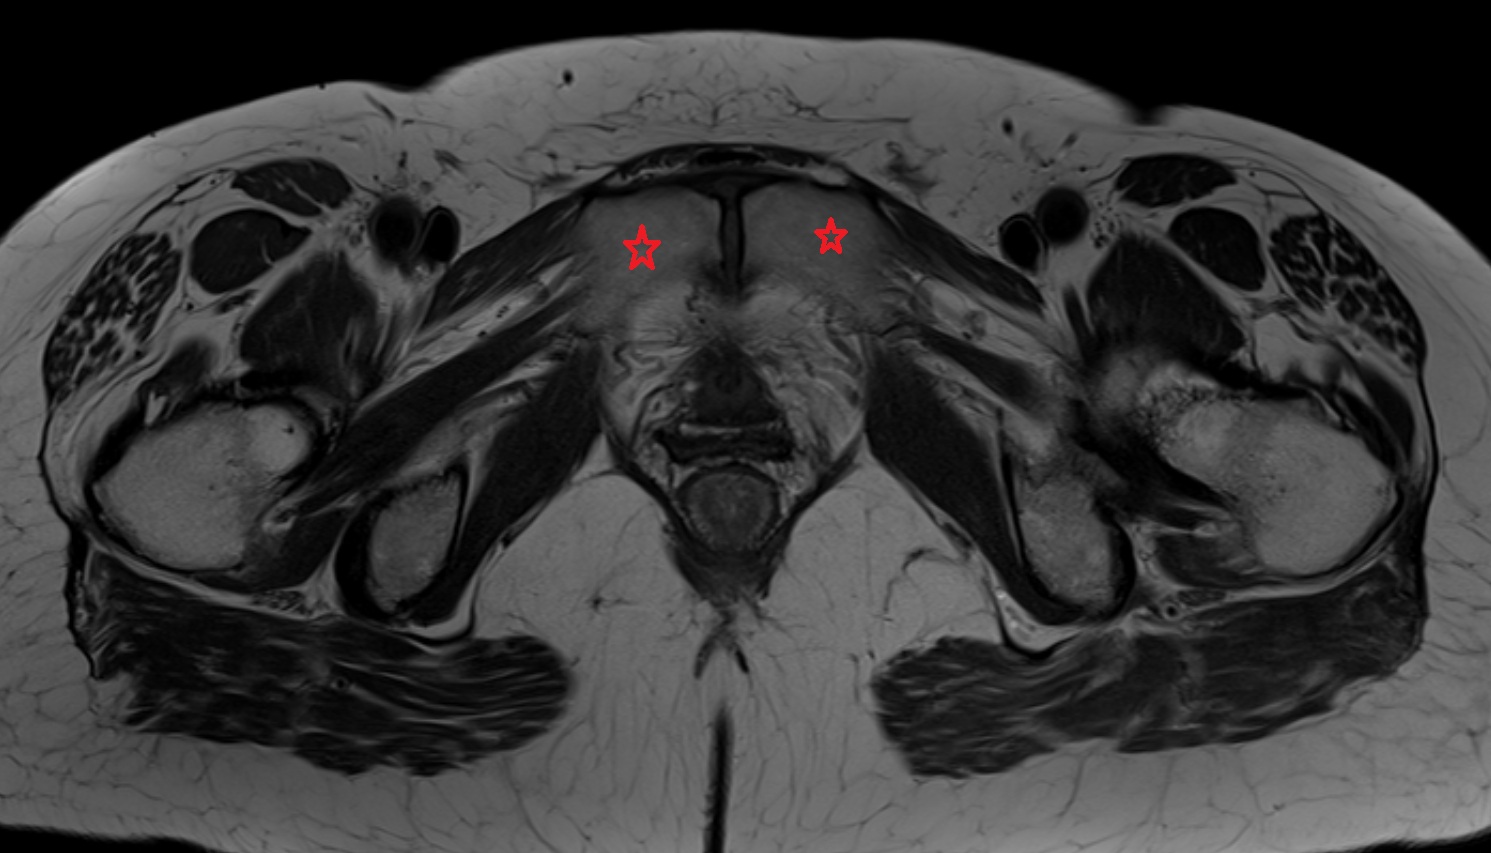

- Corpus cavernosum

- Corpus spongiosum

- Bulb of Penis

- Crus of penis